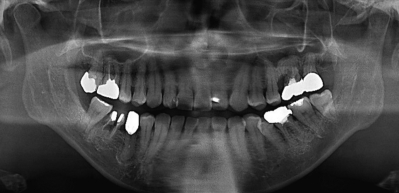

51歳の女性。口腔内の金属修復物に関する精査と加療のため、皮膚科からの紹介により来院した。皮膚科では手掌の疾患に対して副腎皮質ステロイド外用薬の投与を受けているという。初診時の手掌の写真とエックス線写真を別に示す。

まず行うべき対応はどれか。1つ選べ。

e. 歯科用金属のパッチテスト